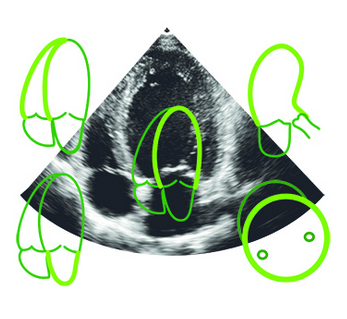

Smart Echo Analyzer for Cardiac Strain & EF

• Automated echocardiogram analysis delivers precise cardiac measurements with minimal variability, providing rapid and reliable insights that support timely clinical decisions and enable comprehensive assessment for improved monitoring and personalized patient care.